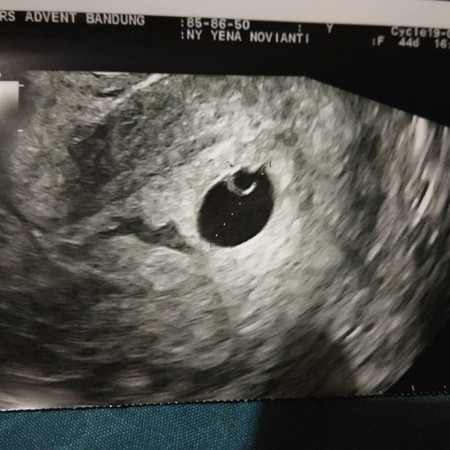

Alhamdulillah setelah usg 4 kali dan kmrn usg transvaginal kantung hamilnya udah terlihat dan udah ada dd utunnya, tapi ada flek bun di sekitar rahimnya?kista aku dah g pikirin dlu skrg aku pikirin babynya..???pernah g bunda dsni pas usg ada fleknya bun? Bahaya g itu buat babynya? Masukan donk bun